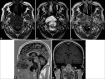

(a-c) Contrast MRI brain. A lobulated T1-weighted hypointense and T2-weighted hyperintense clival mass with moderate heterogeneous contrast enhancement, showing a honeycombing appearance (white arrows). (d) Contrast MRI brain. Extension of the mass into the foramen magnum with compression onto the brainstem. (e) Contrast MRI brain. Inferior extension with dens erosion (white arrows).

(a and b) Contrast MRI brain. Lateral extension of the mass into the right middle cranial fossa (white arrow), right cavernous sinus, and right petrous apex with compression onto the right mesial temporal lobe (black arrow). Posterior extension onto the midbrain was also evident (dotted black arrow). (c) Contrast MRI brain. Superior extension of the mass with compression on pituitary stalk and optic chiasm.